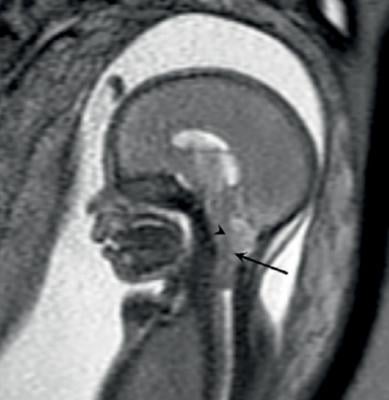

To learn more, Masselli and colleagues used an MRI technique called diffusion-weighted imaging (DWI) to examine pregnant women who had been referred for suspected fetal or placental abnormality. DWI reveals differences in the mobility of water molecules in tissue and the results can be used to create apparent diffusion coefficient (ADC) maps that provide a measure of local cell density. DWI has been increasingly used for abdominal and pelvic diseases, but has not been tested for the evaluation of the uterine cervix in pregnant patients.

The researchers compared differences in ADC values at MRI between two areas of the cervix: the inner, subglandular zone and the outer, stromal area. While stromal ADC and sonographic cervical length showed no difference between both groups, the subglandular ADC was higher in patients with impending delivery, suggesting an increased mobility of water molecules in that area consistent with cervical ripening.

"Our results indicate that a high ADC value recorded at the level of the subglandular area of the cervix is associated with the imminent delivery of asymptomatic patients with a short cervix," Masselli said. "In detail, the subglandular ADC was inversely correlated to the time interval between MRI and delivery and therefore emerged as a powerful imaging biomarker in evaluating patients with impending delivery."